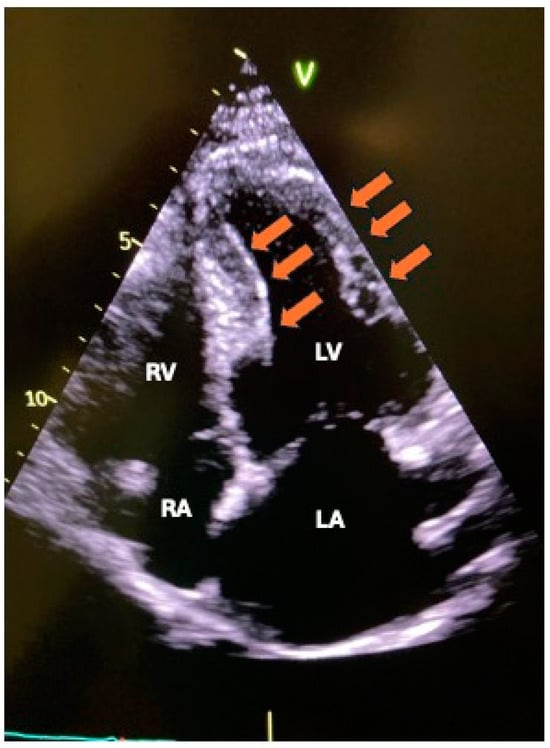

10. Diagnostic Imaging

- L’Angiocola, P.; Donati, R. Cardiac masses in echocardiography: A pragmatic review. J. Cardiovasc. Echography 2020, 30, 5–14. (In English) [Google Scholar] [CrossRef]

- Aggeli, C.; Dimitroglou, Y.; Raftopoulos, L.; Sarri, G.; Mavrogeni, S.; Wong, J.; Tsiamis, E.; Tsioufis, C. Cardiac Masses: The Role of Cardiovascular Imaging in the Differential Diagnosis. Diagnostics 2020, 10, 1088. (In English) [Google Scholar] [CrossRef] [PubMed]

- Xia, H.; Gan, L.; Jiang, Y.; Tang, Q.; Zhang, P.; Tang, X.; Wen, L.; Liu, Z.; Gao, Y. Use of transesophageal echocardiography and contrast echocardiography in the evaluation of cardiac masses. Int. J. Cardiol. 2017, 236, 466–472. (In English) [Google Scholar] [CrossRef]